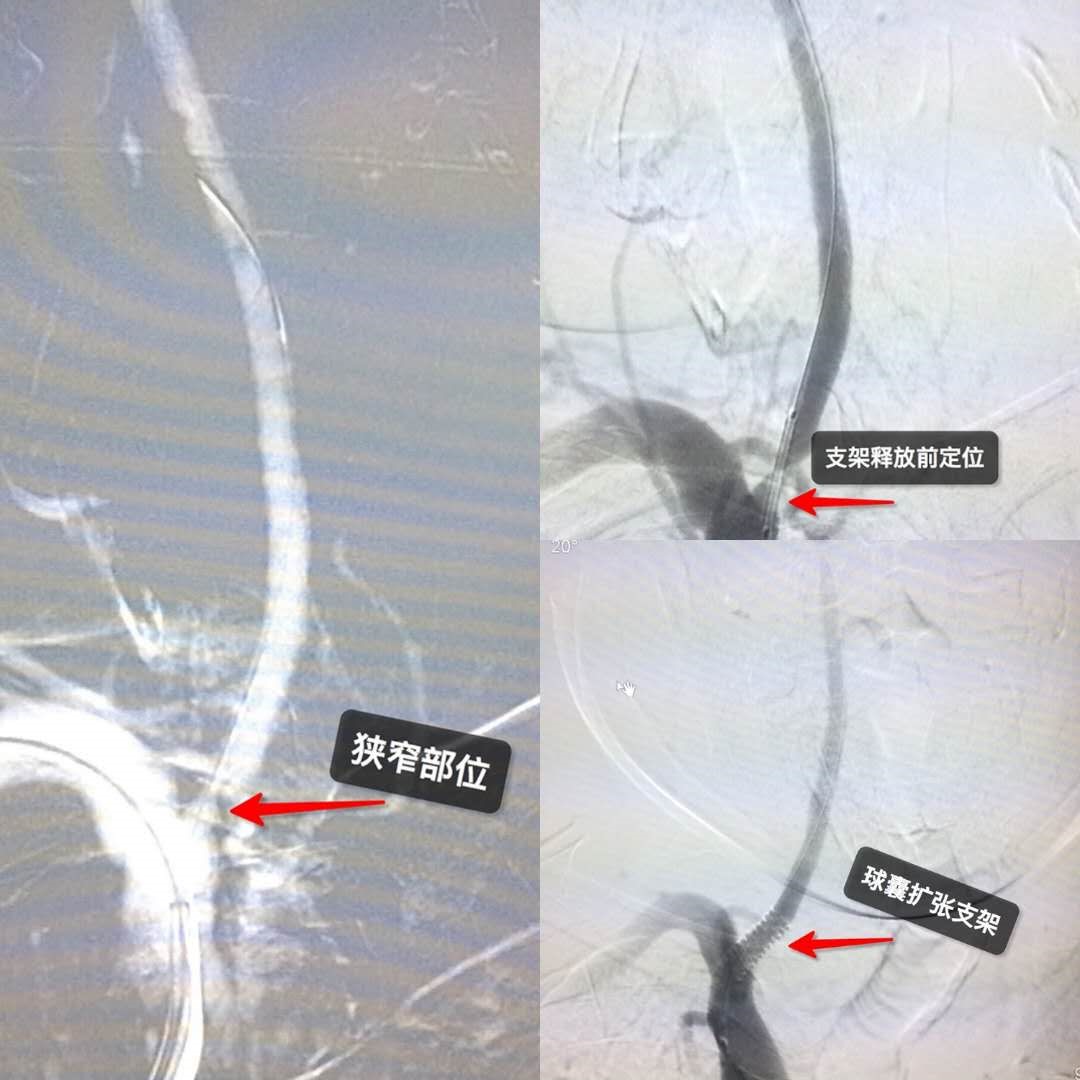

2019年第一周我们的3例复杂脑血管介入手术患者,病人术后恢复良好,可以安全出院了。尤其是脑梗死患者右侧大脑中动脉闭塞再通术难度高风险大为我市首例,至此,我院神经内二科开启了神经介入的新开端。

54岁男性,右侧大脑中动脉慢性闭塞再通术

76岁男性,椎动脉支架植入术

79岁男性,颈动脉支架植入术